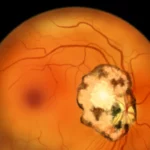

Esta disciplina científica, tal y como afirma el fisioterapeuta Juan Vicente López Díaz (presidente de la fundación Omphis), no sólo se ha fijado en el movimiento macroscópico articular, sino en la motilidad (tendencia o intención de oposición) que se desarrolla en la intimidad del músculo y que, aunque casi inapreciable a la vista es muy patente para la percepción táctil. De esta calidad de la reacción motriz muscular, sobre la que se aplica la atención, y fruto de un análisis adecuado, se desprenden las conclusiones diagnósticas.

En este contexto, la kinesiología podría perfectamente definirse como conocimiento o ciencia de la motilidad reactiva muscular. Y eso es exactamente lo que se percibe en el test muscular de precisión, base de la kinesiología.

Descubre cómo funciona la kinesiología y cómo, a través del test muscular, accedemos a información subconsciente que revela las causas de bloqueos emocionales somatizados en forma de dolor o enfermedades.